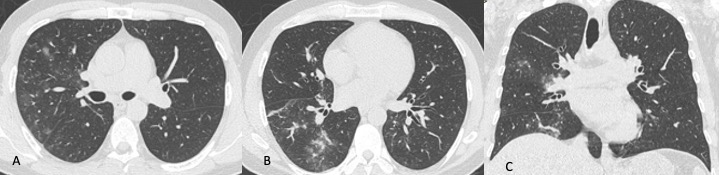

L’esacerbazione acuta (EA) è tra le più gravi complicanze nei pazienti affetti da fibrosi polmonare idiopatica (FPI) costituendo una delle principali cause di morte. Si definisce come deterioramento della funzionalità respiratoria acuto e clinicamente significativo caratterizzato dalla comparsa di alterazioni alveolari diffuse e si diagnostica in base ai seguenti criteri: diagnosi precedente o concomitante di FPI; peggioramento o insorgenza acuta di dispnea tipicamente inferiore ad 1 mese di durata; comparsa di opacità a “vetro smerigliato” e/o aree di consolidazione parenchimale alla TCAR sovrapposte al pattern UIP; deterioramento respiratorio non riconducibile ed insufficienza cardiaca o edema polmonare.

In TCAR l’EA è caratterizzata dalla comparsa di aree a “vetro smerigliato” che si sovrappongono alle alterazioni fibrotiche (Figura 14).

In letteratura sono stati descritti tre pattern principali di EA: periferico, multifocale e diffuso. Nel pattern periferico le aree di aumentata densità si riconoscono nella parte interna della zona periferica adiacenti all’honeycombing subpleurico. Il pattern multifocale è caratterizzato dalla presenza di aree di aumentata densità nelle zone centrali e periferiche, tuttavia, l’interessamento parenchimale ha estensione limitata ed interessa solo alcune zone di polmone. Nel pattern diffuso si osserva aumento della densità del parenchima polmonare esteso sia alle zone periferiche che in quelle centrali. La distinzione di questi tre pattern è clinicamente molto importante; infatti, il pattern diffuso è quello caratterizzato da una prognosi peggiore.

Figura 14: Paziente di sesso femminile, 75 anni, con storia di interstiziopatia polmonare inquadrata come UIP probabile dal 2018. La paziente giunge al Pronto Soccorso per repentino e grave peggioramento della funzionalità respiratoria. Le immagini TCAR assiali (A-B) documentano la presenza in entrambi i polmoni di multiple aree a “vetro smerigliato” con distribuzione diffusa. Dopo aver escluso le ipotesi di edema cardiogeno e di infezione polmonare viene posta diagnosi di esacerbazione di fibrosi polmonare idiopatica.